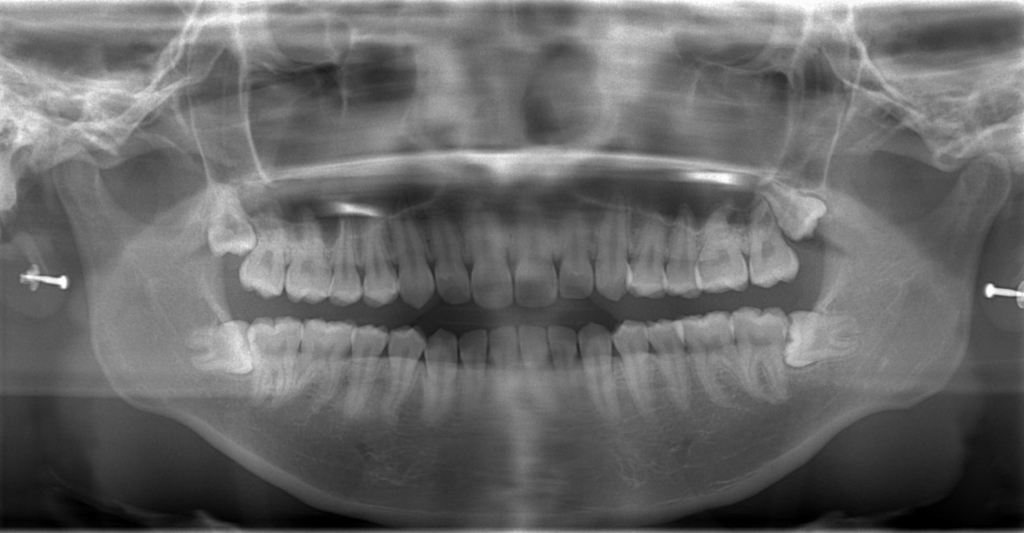

レントゲン写真で確認すると、

この患者さんの場合、

矯正後の状態をレントゲン写真で確認すると、